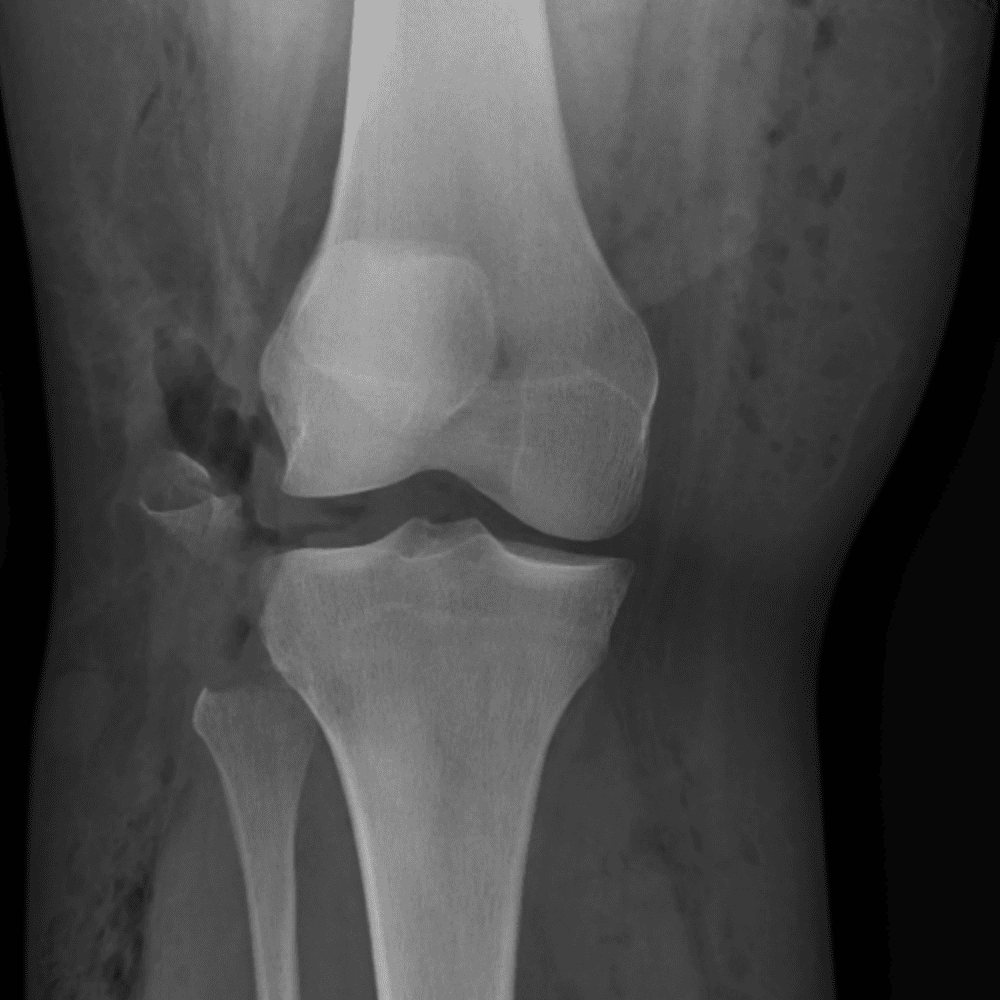

Simula o plantão incluindo casos sutis ou difíceis e alguns normais.